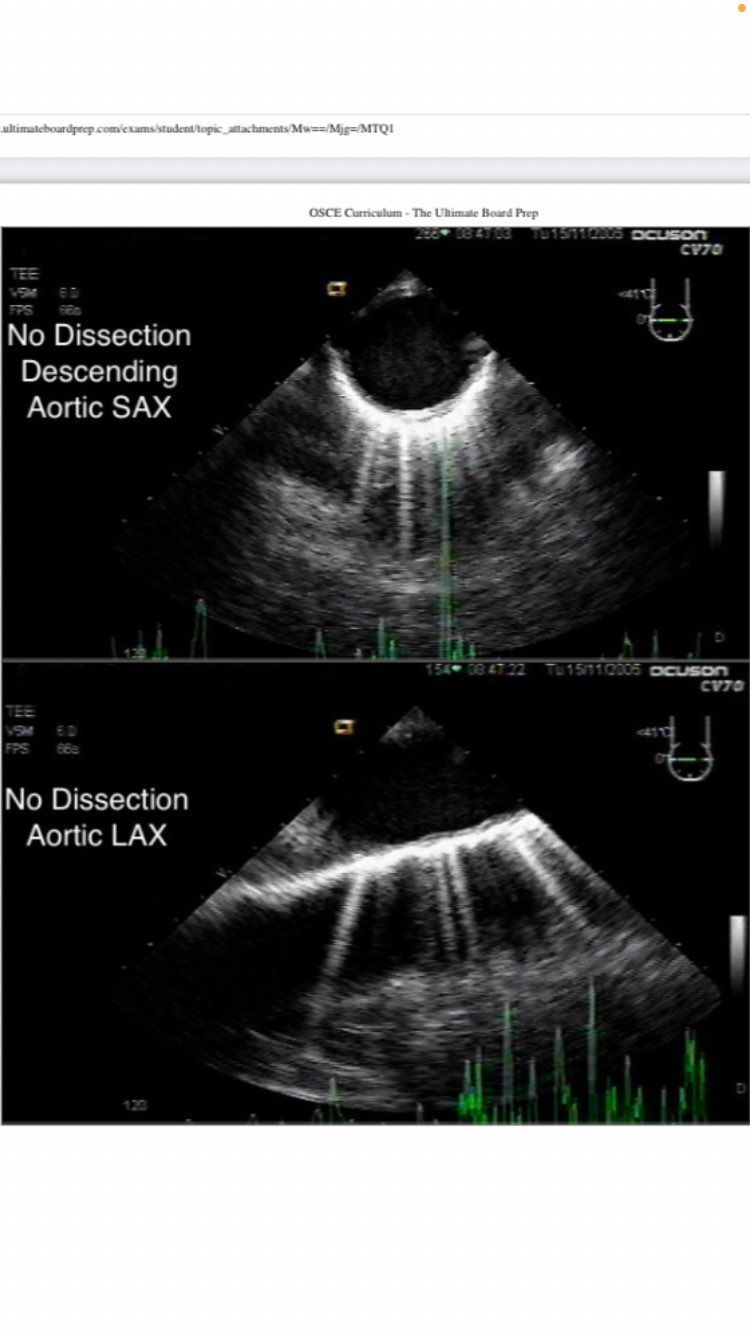

descending aortic SAX and LAX

descending aortic SAX

descending aortic short axis

aortic long axis

NO DISSECTION